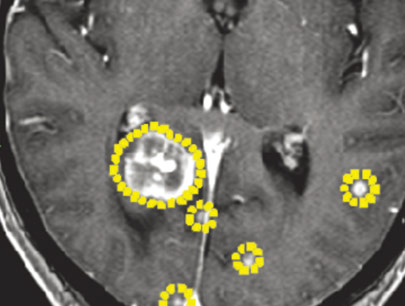

(Perempuan, 14 tahun)

Diagnosis: Malformasi Arteri-Vena Oksipital Kanan

Sebelum Gamma Knife

• Nyeri Kepala

3 bulan Setelah Gamma Knife

• Kebutaan menetap

• Penonjolan mata kiri berkurang

Diameter Nidus: 1.5 cm

Nidus tidak ada